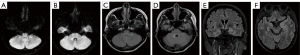

Anti-GAD65 encephalitis

All 4 patients with anti-GAD65 encephalitis were female, with an average onset age of 37±11.1 years, ranging from 26 to 52 years, with a median disease duration of 1,277 days. All patients underwent brain MRI during the acute stage, and 2 of them (50%) showed abnormalities: one patient had T2 FLAIR hyperintensity and mild DWI hyperintensity in the left cerebellopontine crus and right brachium pontine (Figure 7A-7D), the other showed bilateral hippocampal swelling with T2 FLAIR hyperintensity and mild DWI hyperintensity (Figure 7E,7F). Contrast-enhanced scanning was performed on one patient, which showed no pathological enhancement.

Both patients with abnormal MRI were re-examined with brain MRI during the convalescent period, and both revealed improvement with a reduced lesion area and decreased T2 FLAIR and DWI hyperintensity. Table 6 presents the clinical and imaging characteristics of anti-GAD65 encephalitis.

In anti-GAD65 autoimmune neurological diseases characterized by limbic encephalitis or temporal lobe epilepsy (39), the brain MRI findings depend upon the course and severity of the disease. In the acute phase, the common abnormalities are unilateral or bilateral medial temporal lobe swelling and T2 FLAIR hyperintensity, which may progress to hippocampal and frontotemporal lobe atrophy during follow-up (40).

In this study, two of four cases (50%) showed abnormal brain MRI. One showed bilateral hippocampal swelling with T2 FLAIR and DWI hyperintensity, and the clinical manifestation was temporal lobe epilepsy; the other showed T2 FLAIR hyperintensity and DWI mild hyperintensity involving the left cerebellopontine crus and right brachium pontine, and the clinical manifestation was cerebellar ataxia. These results were consistent with the previous studies (39,41,42).